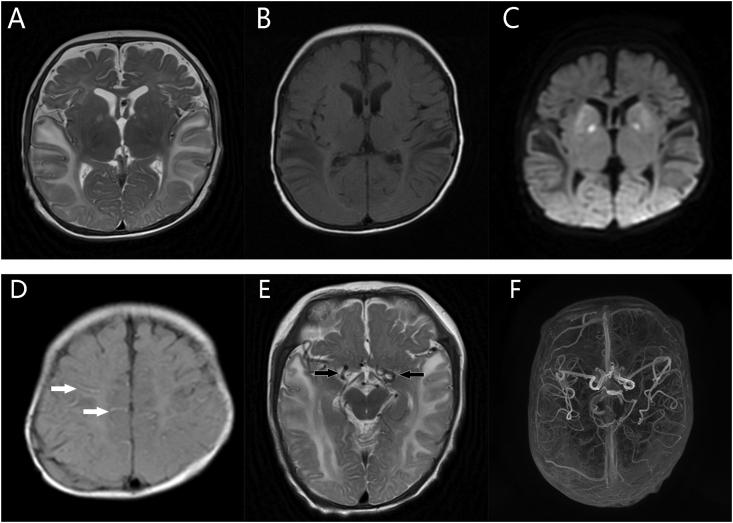

We report a case of Menkes disease. A 4-month-old boy presented with intermittent convulsions for a week. The brain MRI showed excessive tortuosities of intracranial vessels, and radiologists prompted for further examinations to confirm that it was Menkes disease. Patient was advised for biochemical investigations and genetic tests. Reduced level of ceruloplasmin (0.04 g/L; normal range, 0.2-0.6 g/L) was revealed. Genetic testing revealed a missense mutation within exon 18, c.3548 G > A, p.G1183D. This patient was almost misdiagnosed as epilepsy. Fortunately, based on the clues from radiologist, further physical examination and experimental tests were carried out.

We reported the imaging features of a case of Menkes disease, which can provide clinicians with more clues to consider the possibility of this rare disease.